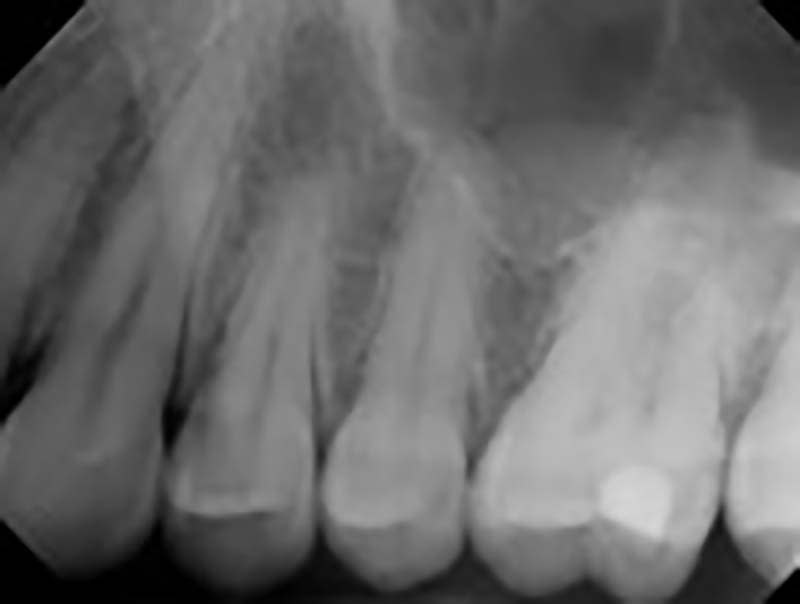

How To Interpret Dental X Rays . Recognizing the signs of healthy teeth and gums and abnormalities like cavities, gum disease, and bone loss is crucial for effective diagnosis and treatment planning.

Recognizing the signs of healthy teeth and gums and abnormalities like cavities, gum disease, and bone loss is crucial for effective diagnosis and treatment planning.